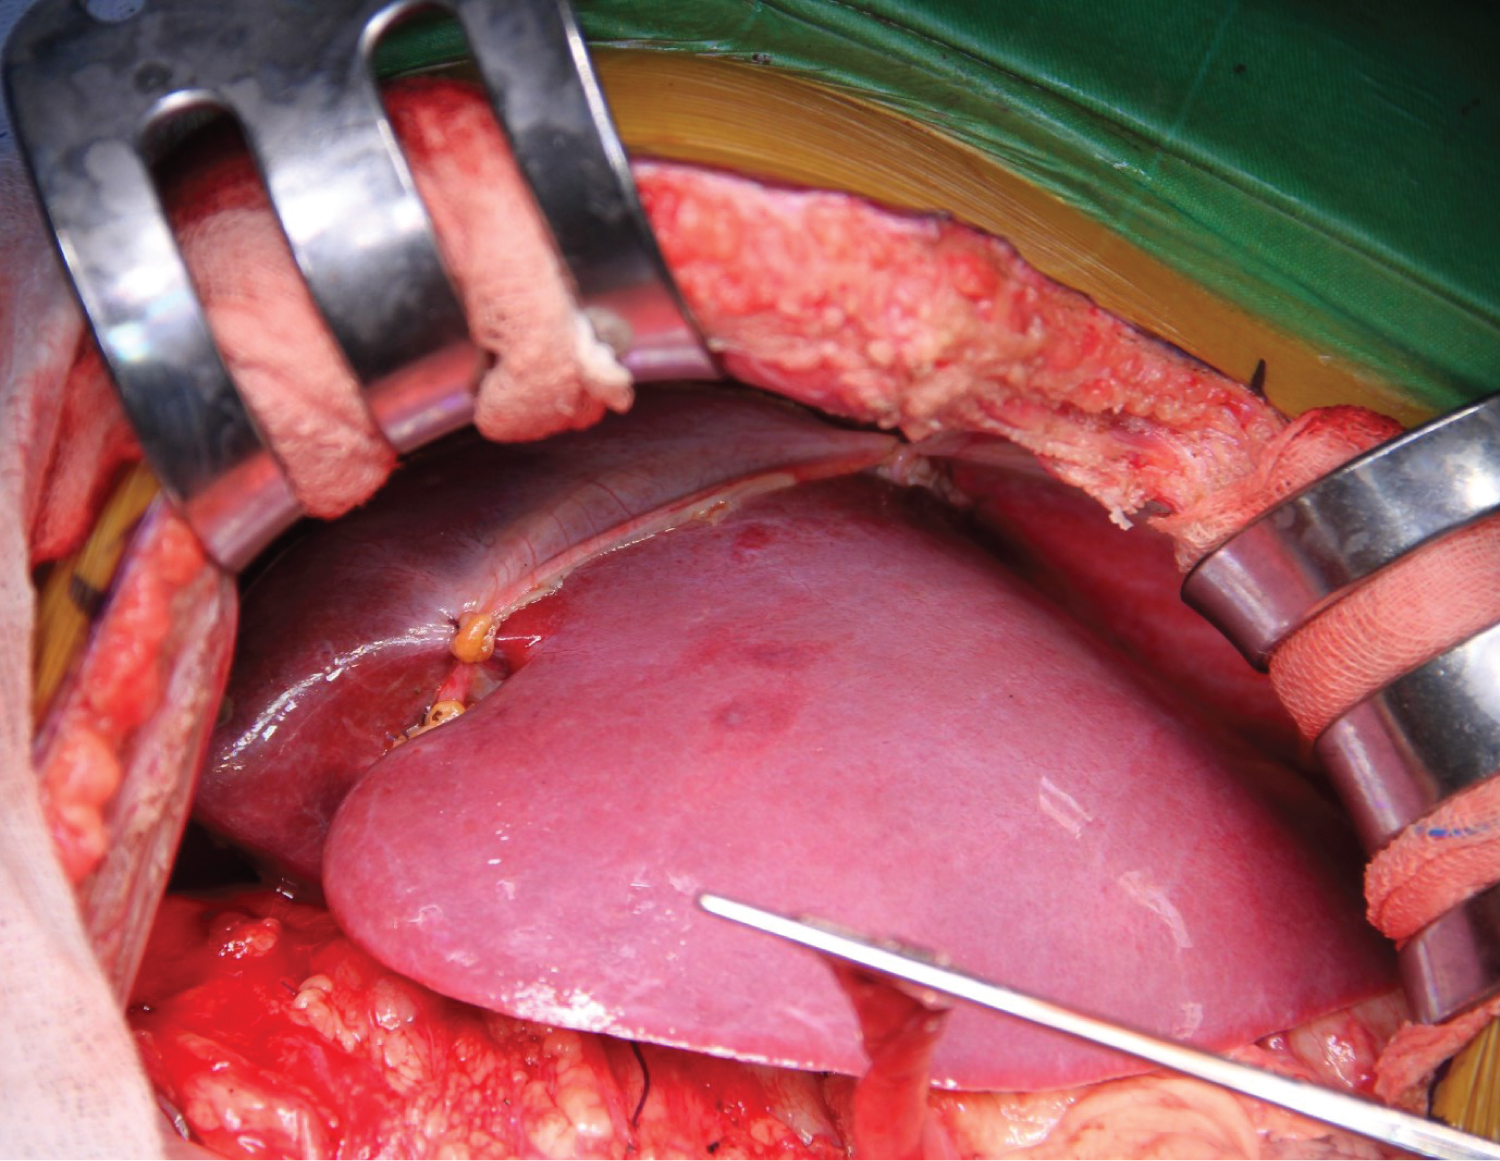

A 6-year-old female (height: 115 cm, weight: 22 kg) patient with pediatric living donor LT for biliary atresia (cirrhosis with portal hypertension) with a pulmonary AVF, HPS, was admitted to an intensive care unit (ICU) transplantation. She had a Kasai operation on the 45 th day after birth to treat biliary atresia. After the Kasai procedure, the patient developed malnutrition due to portal hypertension, hepatosplenomegaly, jaundice, ascites, and esophageal varices. After month 5, dyspnea, platypnea, orthodeoxia, weakness, cyanosis when crying, clubbing, and cyanotic fingertips began to appear. These findings' presence in ESLD patients made us think of HPS, and CE-TTE was then performed, and microbubbles were observed in the left atrium on CE-TTE. A lung perfusion scan revealed an intrapulmonary right-to-left shunt fraction of 25%, and pulmonary arteriography was also diffuse IPVD and pulmonary AVF without capillary phase was detected. In the patient's liver computed tomography (CT)-angiography, diffuse hepatoportal shunt and splenomegaly were found in the liver parenchyma due to the operated biliary atresia (Figure 1). She later developed cirrhosis and was followed up with a diagnosis of cirrhosis until the age of 6 years.

Figure 1: In the patient's liver computed tomography (CT) - angiography, diffuse hepatoportal shunt and splenomegaly were found in the liver parenchyma due to the operated biliary atresia.